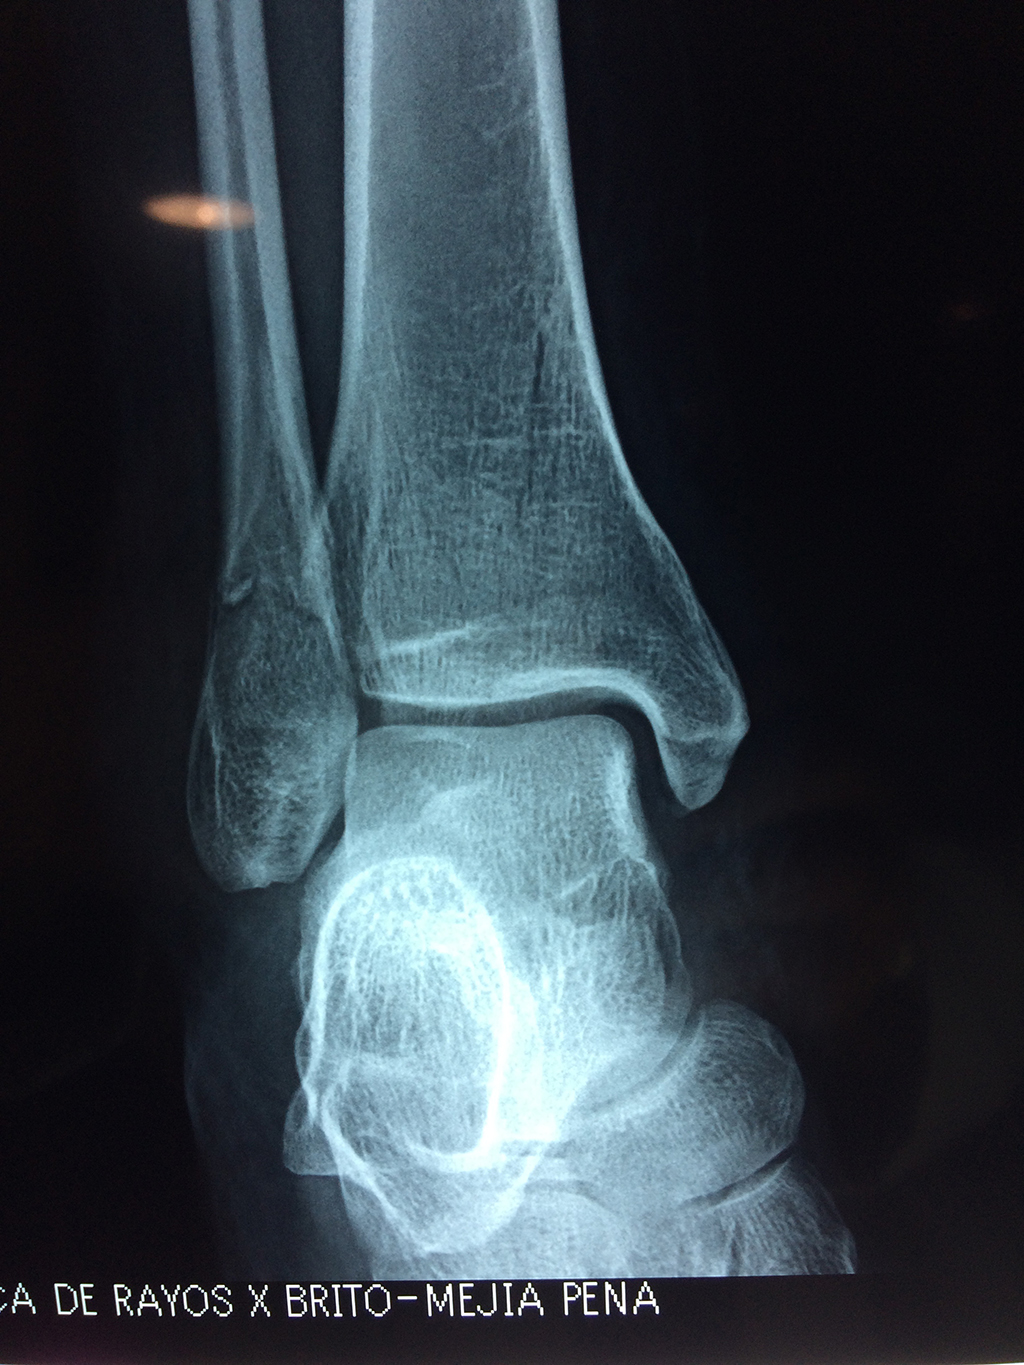

Una fractura de tobillo es la rotura de uno o más de los huesos del tobillo. Estas fracturas pueden ser:

- Los extremos de los huesos están desalineados entre sí (desplazados).

- La fractura se extiende hasta la articulación del tobillo (fractura intra-articular).

Cuando se necesita cirugía, es probable que esta implique el uso de clavijas de metal, tornillos o placas para sostener los huesos en su lugar mientras la fractura se consolida. Los elementos de soporte pueden ser temporales o permanentes.